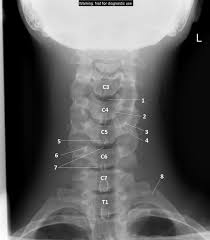

Sie Verwenden Zurzeit Eine Altere Browserversion Und Ihr Website Erlebnis Ist Moglicherweise Nicht Optimal Bitte Ziehen Sie Ein Update In Erwagung Weitere Informationen Bilder Bilder Startseiteausgewahlte Kollektionenfotosvektorgrafikenoffset Bilder from image.shutterstock.com It's commonly done after someone has been in an automobile or other accident. Enter search terms and tap the search button. Please understand that our phone lines must be clear for urg. Here's what to expect with this painless procedure and why your dentist may recommend it. This procedure may be used to diagnose back or neck pain, fractures or broken bones, arthritis, degeneration of the disks, tumors, or other problems. They show pictures of your internal tissues, bones, and organs.

This procedure may be used to diagnose back or neck pain, fractures or broken bones, arthritis, degeneration of the disks, tumors, or other problems. Enter search terms and tap the search button. They show pictures of your internal tissues, bones, and organs. Please understand that our phone lines must be clear for urg. Here's what to expect with this painless procedure and why your dentist may recommend it.